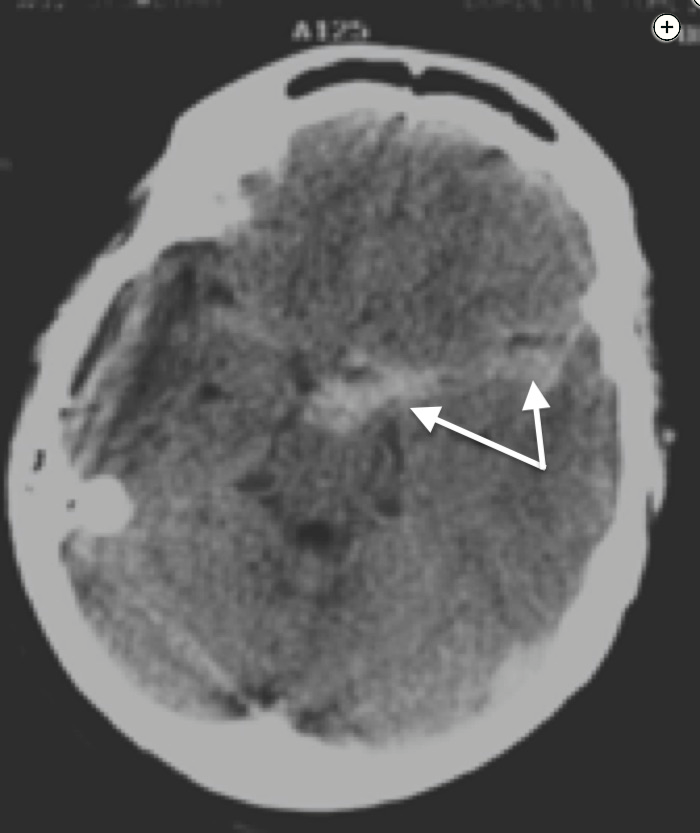

In this patient, the CT scan shows bright signal in the cerebrospinal fluid spaces around the brain parenchyma (the subarachnoid space), which represents blood outside of blood vessels (Figure 2, white arrows).

Noncontrast CT scan of the head showing subarachnoid hemorrhage (arrows).

A 44-year-old man presents with acute onset of headache and neck stiffness. The CT scan is shown (Figure 1). A CT angiogram and a digital subtraction angiogram of the brain show no evidence of a cerebral aneurysm. The ICU and hospital course are uneventful. At day 7, a repeat cerebral angiogram shows no evidence of aneurysm. What is the next appropriate step in the evaluation?